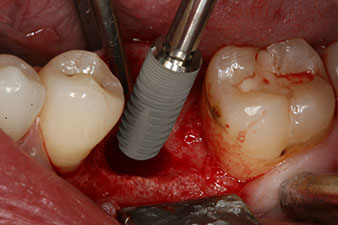

Implantat

Abb. 3: Nach Aufbereitung mit dem Implantmed Implantologiemotor wird ein Implantat (Durchmesser 4 mm, Länge 12 mm) bei einem Drehmoment von 43 Ncm maschinell eingeschraubt.

Nach gründlicher Entfernung des Granulationsgewebes wurde das Implantat wie geplant eingebracht (blueSky, bredent).